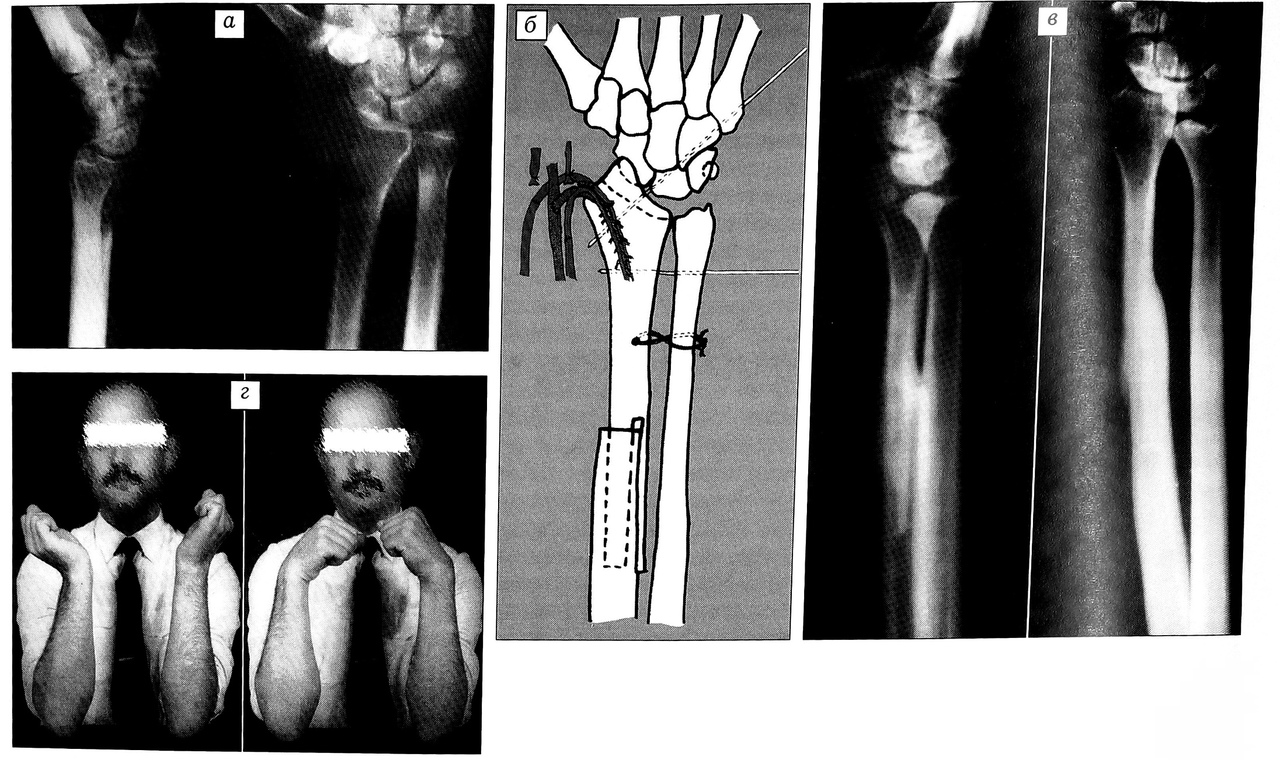

Больной А., 25 лет, поступил в ЦИТО по поводу гигантоклеточной опухоли дистального метаэпифиза лучевой кости левого предплечья. Болен в течение 6 мес. На рентгенограммах (рис. 3, а) определяется патологический очаг в метаэпифизе лучевой кости с разрушением кортикальной пластинки и выходом процесса в мягкие ткани по ладонной поверхности лучевой кости.

17.11.81 двумя бригадами хирургов выполнено оперативное вмешательство. Первой бригадой из ладонного доступа выделены лучевая артерия с сопровождающими венами, срединный нерв, сухожилия и произведено абластичное удаление очага поражения — резекция дистального суставного конца лучевой кости на протяжении 7 см вместе с интимно связанным с опухолью квадратным пронатором предплечья. Костномозговой канал рассверлен на глубину 5 см. Одновременно второй бригадой осуществлен забор трансплантата из проксимального отдела малоберцовой кости длиной 12 см. Произведен остеосинтез по методу Коржа—Талышинского в модификации С.Т. Зацепина с дополнительной фиксацией трансплантата спицами и лавсановой петлей. Выполнен анастомоз конец в бок между a. genu inferior lateralis и a. radialis, одна вена сшита со спутницей лучевой артерии, другая — с подкожной веной предплечья (рис. 3, б).

Через 1,5 года после операции отмечается умеренное ограничение движений в кистевом суставе. На рентгенограммах нормальная костная структура эпифиза пересаженной малоберцовой кости (рис. 3, в, г).